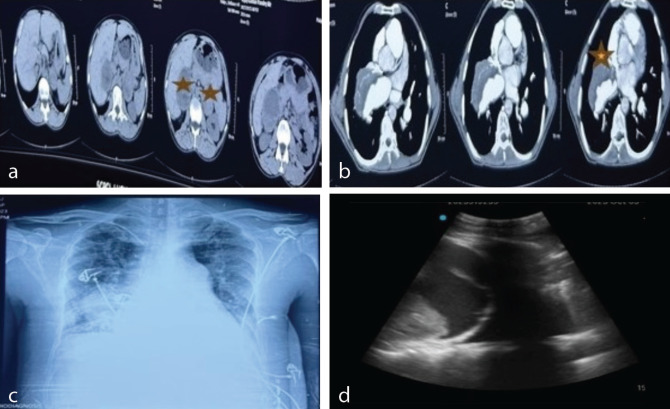

多发性内分泌肿瘤2A型(MEN2A),与嗜铬细胞瘤和甲状腺髓样癌相关。如果这些患者患有先天性心脏病(CHD),手术可能会很复杂。如今,越来越多的冠心病患者在高龄时进行非心脏手术,这给麻醉师带来了独特的挑战。我们在此报告一名44岁男性,患有艾森曼格综合征(ES)和MEN2A,计划进行双侧肾上腺切除术和甲状腺切除术。ES患者在非心脏手术中需要细致和目标导向的管理,这取决于肺动脉高压、紫绀和右室功能障碍。

Multiple endocrine neoplasia type 2A (MEN2A), is associated with pheochromocytoma and medullary carcinoma of the thyroid. A surgical procedure in these patients can be complicated if they have any congenital heart disease (CHD). Nowadays, CHD patients are increasingly presenting at advanced age for non-cardiac surgeries, posing unique challenges to anesthesiologists. We hereby present a 44-year-old male with Eisenmenger syndrome (ES) and MEN2A, scheduled for bilateral adrenal excision and thyroidectomy. Patients with ES require meticulous and goal-directed management during non-cardiac surgery, depending upon pulmonary hypertension, cyanosis, and right ventricular dysfunction.